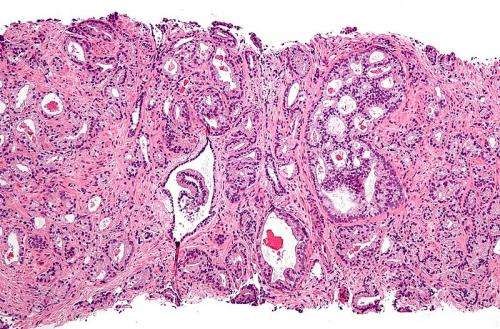

前列腺癌放疗,前列腺癌放射治疗科普前列腺癌是最常见的男性泌尿生殖系统恶性肿瘤之一,发达国家居男性恶性肿瘤发病率首位。2019年国家癌症中心发布的数据显示:前列腺癌发病率居男性恶性肿瘤的第6位,死亡率居第10位。01、前列腺癌可以放疗吗前列腺癌主要治疗方法为手术、放疗、内分泌治疗,因此前列腺癌可以放疗。局限性前列腺癌患者进行根治性手术和放疗可治愈;部分年纪较大